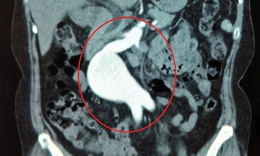

Thành tựu y khoa - 10/10/2025 19:45SKĐS - Bệnh viện TWQĐ 108 mới đây đã điều trị thành công khối phình khổng lồ của động mạch thận ở rốn thận cho nữ bệnh nhân 37 tuổi. Trong quá trình phẫu thuật bệnh viện đã áp dụng kỹ thuật ghép thận tự thân. Đây là ca đầu tiên được thực hiện tại Việt Nam được ghi nhận.

Y học 360 - 11/09/2019 14:07SKĐS - Thấy đau lưng, tự lái xe máy đi khám, đến khi nhận kết quả chẩn đoán hình ảnh, ông V mới tá hỏa khi được các bác sĩ thông báo nguyên nhân dẫn đến tình trạng đau lưng kéo dài là do một túi phình động mạch khổng lồ gây chèn ép.

Camera bệnh viện - 23/08/2018 10:36SKĐS - Bệnh nhi 11 tuổi ở Phú Yên bị ho ra máu, nghi ngờ lao phổi nhưng qua CT Scan ngực, các bác sĩ lại phát hiện túi phình động mạch phổi có khả năng vỡ gây tử vong.